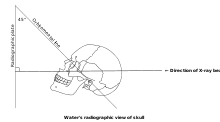

Waters' view (also known as the occipitomental view) is a radiographic view of the skull. It is commonly used to get a better view of the maxillary sinuses. An x-ray beam is angled at 45° to the orbitomeatal line. The rays pass from behind the head and are perpendicular to the radiographic plate. Another variation of the waters places the orbitomeatal line at a 37° angle to the image receptor. It is named after the American radiologist Charles Alexander Waters.

Procedure

Typically, the x-ray beam is angled at 45° to the orbitomeatal line.[3] Another variation of the waters places the orbitomeatal line at a 37° angle to the image receptor,[4] or 30°.[5]